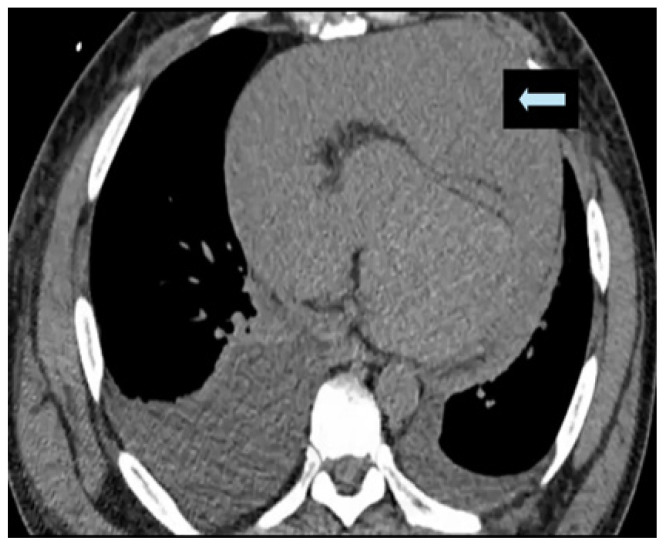

Metastatic Cardiac Angiosarcoma Presenting as Superior Vena Cava Syndrome and Cardiac Tamponade.